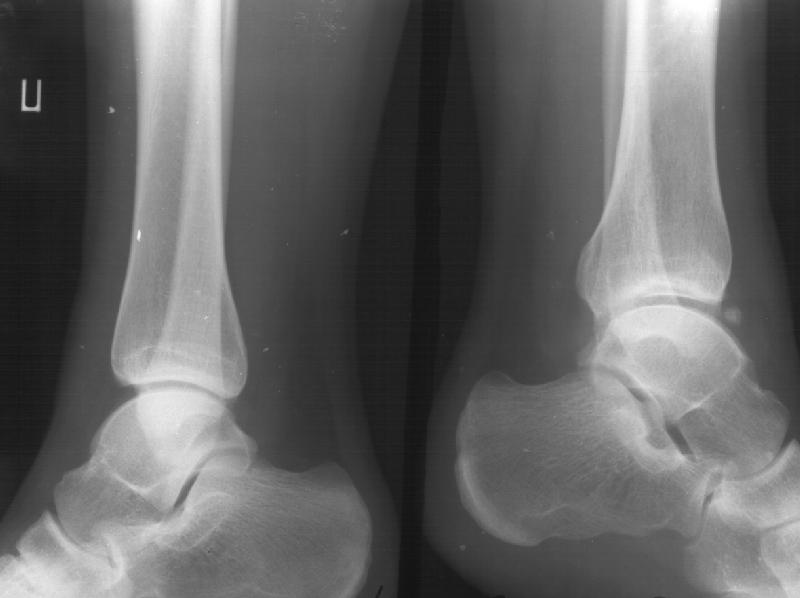

Девочка 14 лет полтора года назад оперирована в детской больнице по поводу спирального перелома костей голени (снимок 1)- выполнен закрытый остеосинтез стержнем Богданова, введенным ретроградно с медиальной стороны (снимок 2). Фиксатор после сращения удален

(см. снимки 3 и 4, после удаления, для сравнения со здоровой стороной, фас - стоя с нагрузкой на обе ноги). В настоящее время беспокоят боль и отеки в области голеностопного сустава при нагрузках, после ходьбы. В покое и ночью боли нет. Амплитуда движений в голеностопном суставе практически полная. Имеется заметная боковая нестабильность, т.е. несостоятельность дельтовидной связки и межберцоого синдесмоза. Складывается впечатление, что при остеосинтезе был отколот и смещен в сторону сустава костный фрагмент позади внутренней лодыжки, увеличилось смещение отломка заднего края, что привело к столь ранним проявлениям деформирующего артроза. Встает вопрос - что делать сейчас? Артодез - наверно, рано. Ревизию сустава, моделирующую резекцию? Пластику связок? Что-то еще? Заранее спасибо.